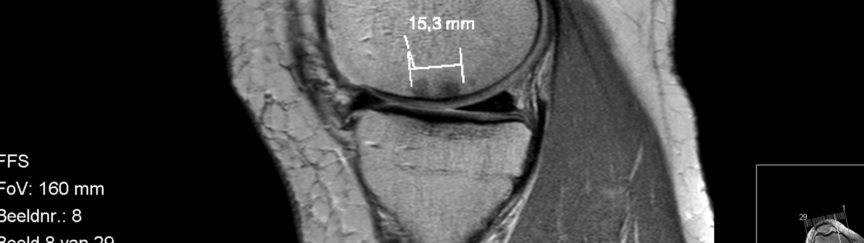

Chondropathie noemen ze dat. ook wel bekend als artrose of versleten en/of kapot kraakbeen. Graad 1 valt wel mee dat kunnen ze eigenlijk alleen zien als ze in de knie kijken en er met een haakje op drukken. Het kraakbeen is zacht en het verend vermogen is dan minder. Door naar graad 2, met wat scheutjes wat onregelmatigheden in de structuur. Ook is de dikte minder dan de gebruikelijke 4mm. Graad 3 met scheuren en losse stukken kraakbeen. De dikte is dan ongeveer nog de helft. Uiteindelijk graad 4. Dat is plat gezegd ‘bot-op-bot’. Komt vaak voor vijftien tot twintig jaar na een meniscus operatie. Laat dat nu precies kloppen. Een jaar of vijf geleden begonnen deze problemen, nadat ik op mijn negentiende de eerste keer ben geopereerd, aan mijn meniscus destijds. In 2011 ben ik de eerste keer geopereerd aan kapot kraakbeen, een dikke twintig jaar later. Mijn laatste operatie in 2013 hebben ze er weer stukken uit verwijderd en met microfracturing proberen enigzins te herstellen. bijna 3 maanden op krukken en eigenlijk weinig bereikt. Toen was het al graad 4, zowel mediaal (binnenkant) als lateraal (buitenkant) en een femorale groeve met graad 3. Dat laatste zal wel niet veel beter zijn geworden de afgelopen jaren omdat mijn knieschijf regelmatig grote moeite heeft om netjes in het gareel te blijven.